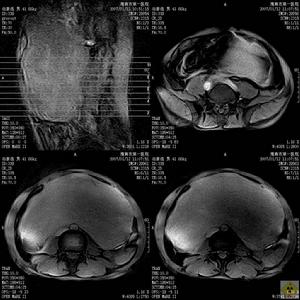

非轉移性癌性神經肌肉瘤大多位於近側的1/2,即賁門、底區域,其次是體部,巨大的平滑肌肉瘤。

1.大體形態腫瘤大小不一,可單發或多發,直徑從數毫米至十餘厘米,甚或超過20cm,一般直徑在10cm左右,呈結節狀或分葉狀。較小的平滑肌肉瘤多位於壁內,外觀與平滑肌瘤相似,可向腔內隆起呈廣基無蒂,少數可呈蒂狀,其表面的黏膜往往有潰瘍形成,小的較表淺,直徑約0.2cm,大的可達5cm以上。較大的腫瘤常向腔外突出,少數呈啞鈴形,並可侵犯周圍臟器和組織。一般認為,腫瘤呈結節狀,向腔內或腔外生長,有囊性變或大而不規則的潰瘍者,多為平滑肌肉瘤。切面呈淡褐色或黃白色,經甲醛乙醇(福馬林)固定後呈淡褐紅色,可見到編織狀纖維束,並有壞死、出血及囊性變。